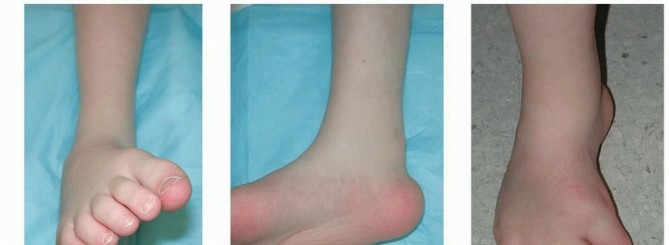

NATURAL HISTORY Residual deformities are usually encountered within the first year after initial treatment and generally before the age of 5 years, even in congenital clubfeet that had been fully corrected since the first month of life.Residual forefoot adduction and supination are common deformities after nonoperative treatment and can also be seen after initial operative repair. They can result from undercorrection at the time of the primaryintervention. 13Correction of resistant congenital clubfoot often requires more than one surgery, not because of a “failed initial intervention,” but because the dynamic muscle imbalances may not be fully manifest at the time of the initial intervention. Thus, the need for an additional operation can be perceived as part of the natural history ofcongenital clubfoot. 12If left untreated, the dynamic deformity may become stiff and the foot tends to invert.When inversion deformity is combined with residual equinus deformity, hindfoot varus may recur ( FIG 4). ## PATIENT HISTORY AND PHYSICAL FINDINGS Residual deformity is more likely in patients who have clubfoot as a result of myelomeningocele or other neuromuscular syndromes and genetic disorders such as Larsen syndrome. Therefore, it is important to consider neurologic causes, such as tethered cord, when confronted with residual deformity.Recurrent deformity may be found in children with only four toes on the affected foot, as these individuals may have absence of the peroneal muscle group (similar to that seen in fibular hemimelia), thus leaving them prone to recurrence.Recurrent deformity may be suspected prior to treatment in newborns with curled toes and no active toe dorsiflexion when scratching the plantar aspect of the foot. In those infants that have been treated with the Ponseti method, later recurrence may be heralded by scratching the bottom of the foot that leads to more supination than dorsiflexion.One of the first clinical signs of recurrence is a dynamic inversion of the foot with slight equinus. Equinus may be difficult to quantify, as midfoot breech will often accommodate and hide the hindfoot equinus ( FIG 5).Residual deformity most frequently occurs in severe or atypical cases, which are often associated with a small calf size. These children may also have short, fat feet with a deep plantar crease that extends from the medial border

to the lateral border of the foot and a shortened first ray. These findings are consistent with severe or atypical clubfeet (often termed complex clubfoot ) that have a propensity for residual deformity. Illustration 7 for Why Anterior Tibialis Muscle Transfer Fixes Clubfoot --- Illustration 8 for Why Anterior Tibialis Muscle Transfer Fixes Clubfoot ### FIG 5 • Examination findings of residual supination and equinus deformity. A. Forefoot supination. B. Hindfoot equinus. C. Anterior view combined forefoot supination and hindfoot equinovarus. D. Posterior view combined forefoot supination and hindfoot equinovarus. In maximum pronation or maximum supination, the navicular-medial malleolar distance is decreased compared to the normal foot. In fact, the medial malleolus can be difficult to delineate because it is in contact with the navicular. The navicular malleolar distance demonstrates the extent of medial subluxation.It is important to examine gait when possible.During examination of gait, the clinician should identify whether the tibialis anterior is a dynamic supinator; this is best observed in swing phase when no antagonist muscles contract.This finding will confirm the appropriateness of surgery.The strength of the tibialis anterior is tested. With dynamic supination deformity, the supinator action of the anterior tibialis muscle will overpower the dorsiflexor action, thus demonstrating the appropriateness of surgery. In addition, good power is needed for a successful transfer.The clinician should evaluate for other deformities, such as equinus, cavus, varus, adductus, and tibial torsion.Range of motion of the ankle is examined. Transfer will work only as long as there is no fixed contracture of the ankle or heel cord. ## IMAGING AND OTHER DIAGNOSTIC STUDIES Anteroposterior (AP) and lateral radiographs may be helpful to study and quantify various deformities.AP radiographs will demonstrate medial deviation of the metatarsals, which can indicate residual medial displacement of navicular, which is yet to ossify ( FIG 6).On an AP radiograph of normal feet, the line drawn through the long axis of the talus should point to the first metatarsal, whereas the line drawn through the long axis of the calcaneus should point toward the fourth metatarsal.In clubfeet, these lines become more parallel, depicting “stacking” of the talus and calcaneus.Forced maximum dorsiflexion lateral radiographs may reveal hindfoot equinus with midfoot breech.Stacking of the metatarsals on the lateral radiograph identifies the presence of residual forefoot supination (a decreased talocalcaneal angle).Ultrasound evaluation of the foot is not done routinely. However, experimental studies have demonstrated that this technique is capable of documenting the location of the navicular in relationship to the head of the talus. The navicular is subluxated plantarward and medially on the head of the talus.Similarly, MRI can be performed to completely identify the relationships of the cartilaginous bones and the size and presence of the lateral leg muscles.This technology is rarely clinically used, as orthopaedists are aware of the classic deformities that are associated with recurrence and the increased risk of general anesthesia for a childhood MRI scan may not be justified. ## DIFFERENTIAL DIAGNOSIS Residual deformities in clubfoot may be due to unrecognized tarsal coalitions or other conditions in syndromic clubfoot, severe, or complex clubfeet.Unexpected and rapid recurrent deformity in children with previously corrected feet and with known myelomeningocele may be a result of continued neurologic involvement, such as tethering of the spinal cord.